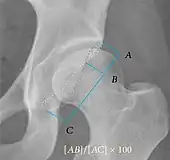

| Crossing ratio | ![]() |

Percentage of acetabular walls crossing. Normal acetabulum is oriented in anteversion. Its value ranges from 15 to 20° in the equatorial plane of the acetabulum and decreases gradually towards the acetabular roof, where normal values range from 0 to 5°. Retroversion of the upper part of the acetabulum has been related with pincer type impingement. In radiography the presence of a "crossover sign" is produced when the posterior wall of the acetabulum crosses the anterior wall before reaching the acetabular roof. It is a sign of acetabular retroversion and it has been linked with overcoverage and pincer impingement. Nevertheless, this sign has been described in 6% of the normal population. Therefore, more important than its presence is the percentage of crossing. | <20%

|